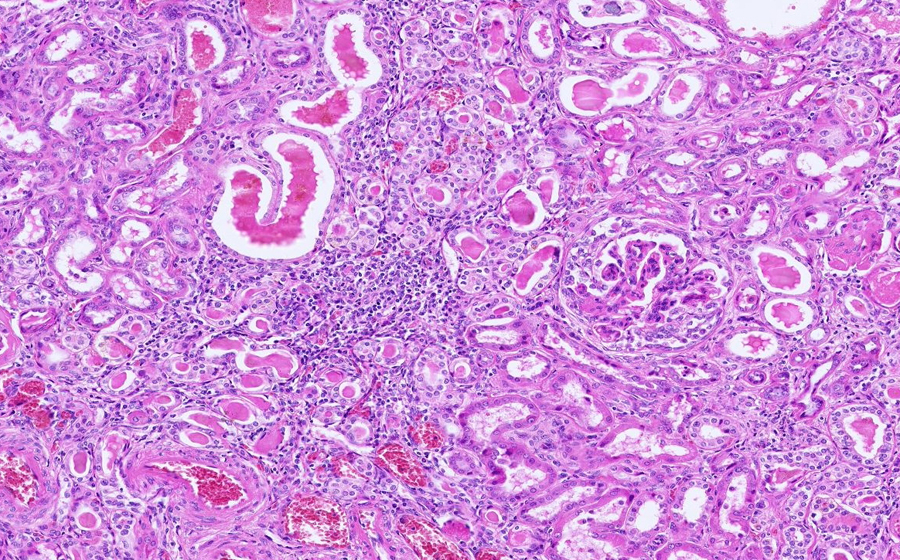

Image 2 - 12.5X

Slide 3 - Image 2